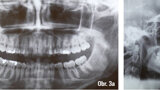

Lingvální zámky 3M™ Incognito™ System a kombinovaná ortodontickochirurgická terapie